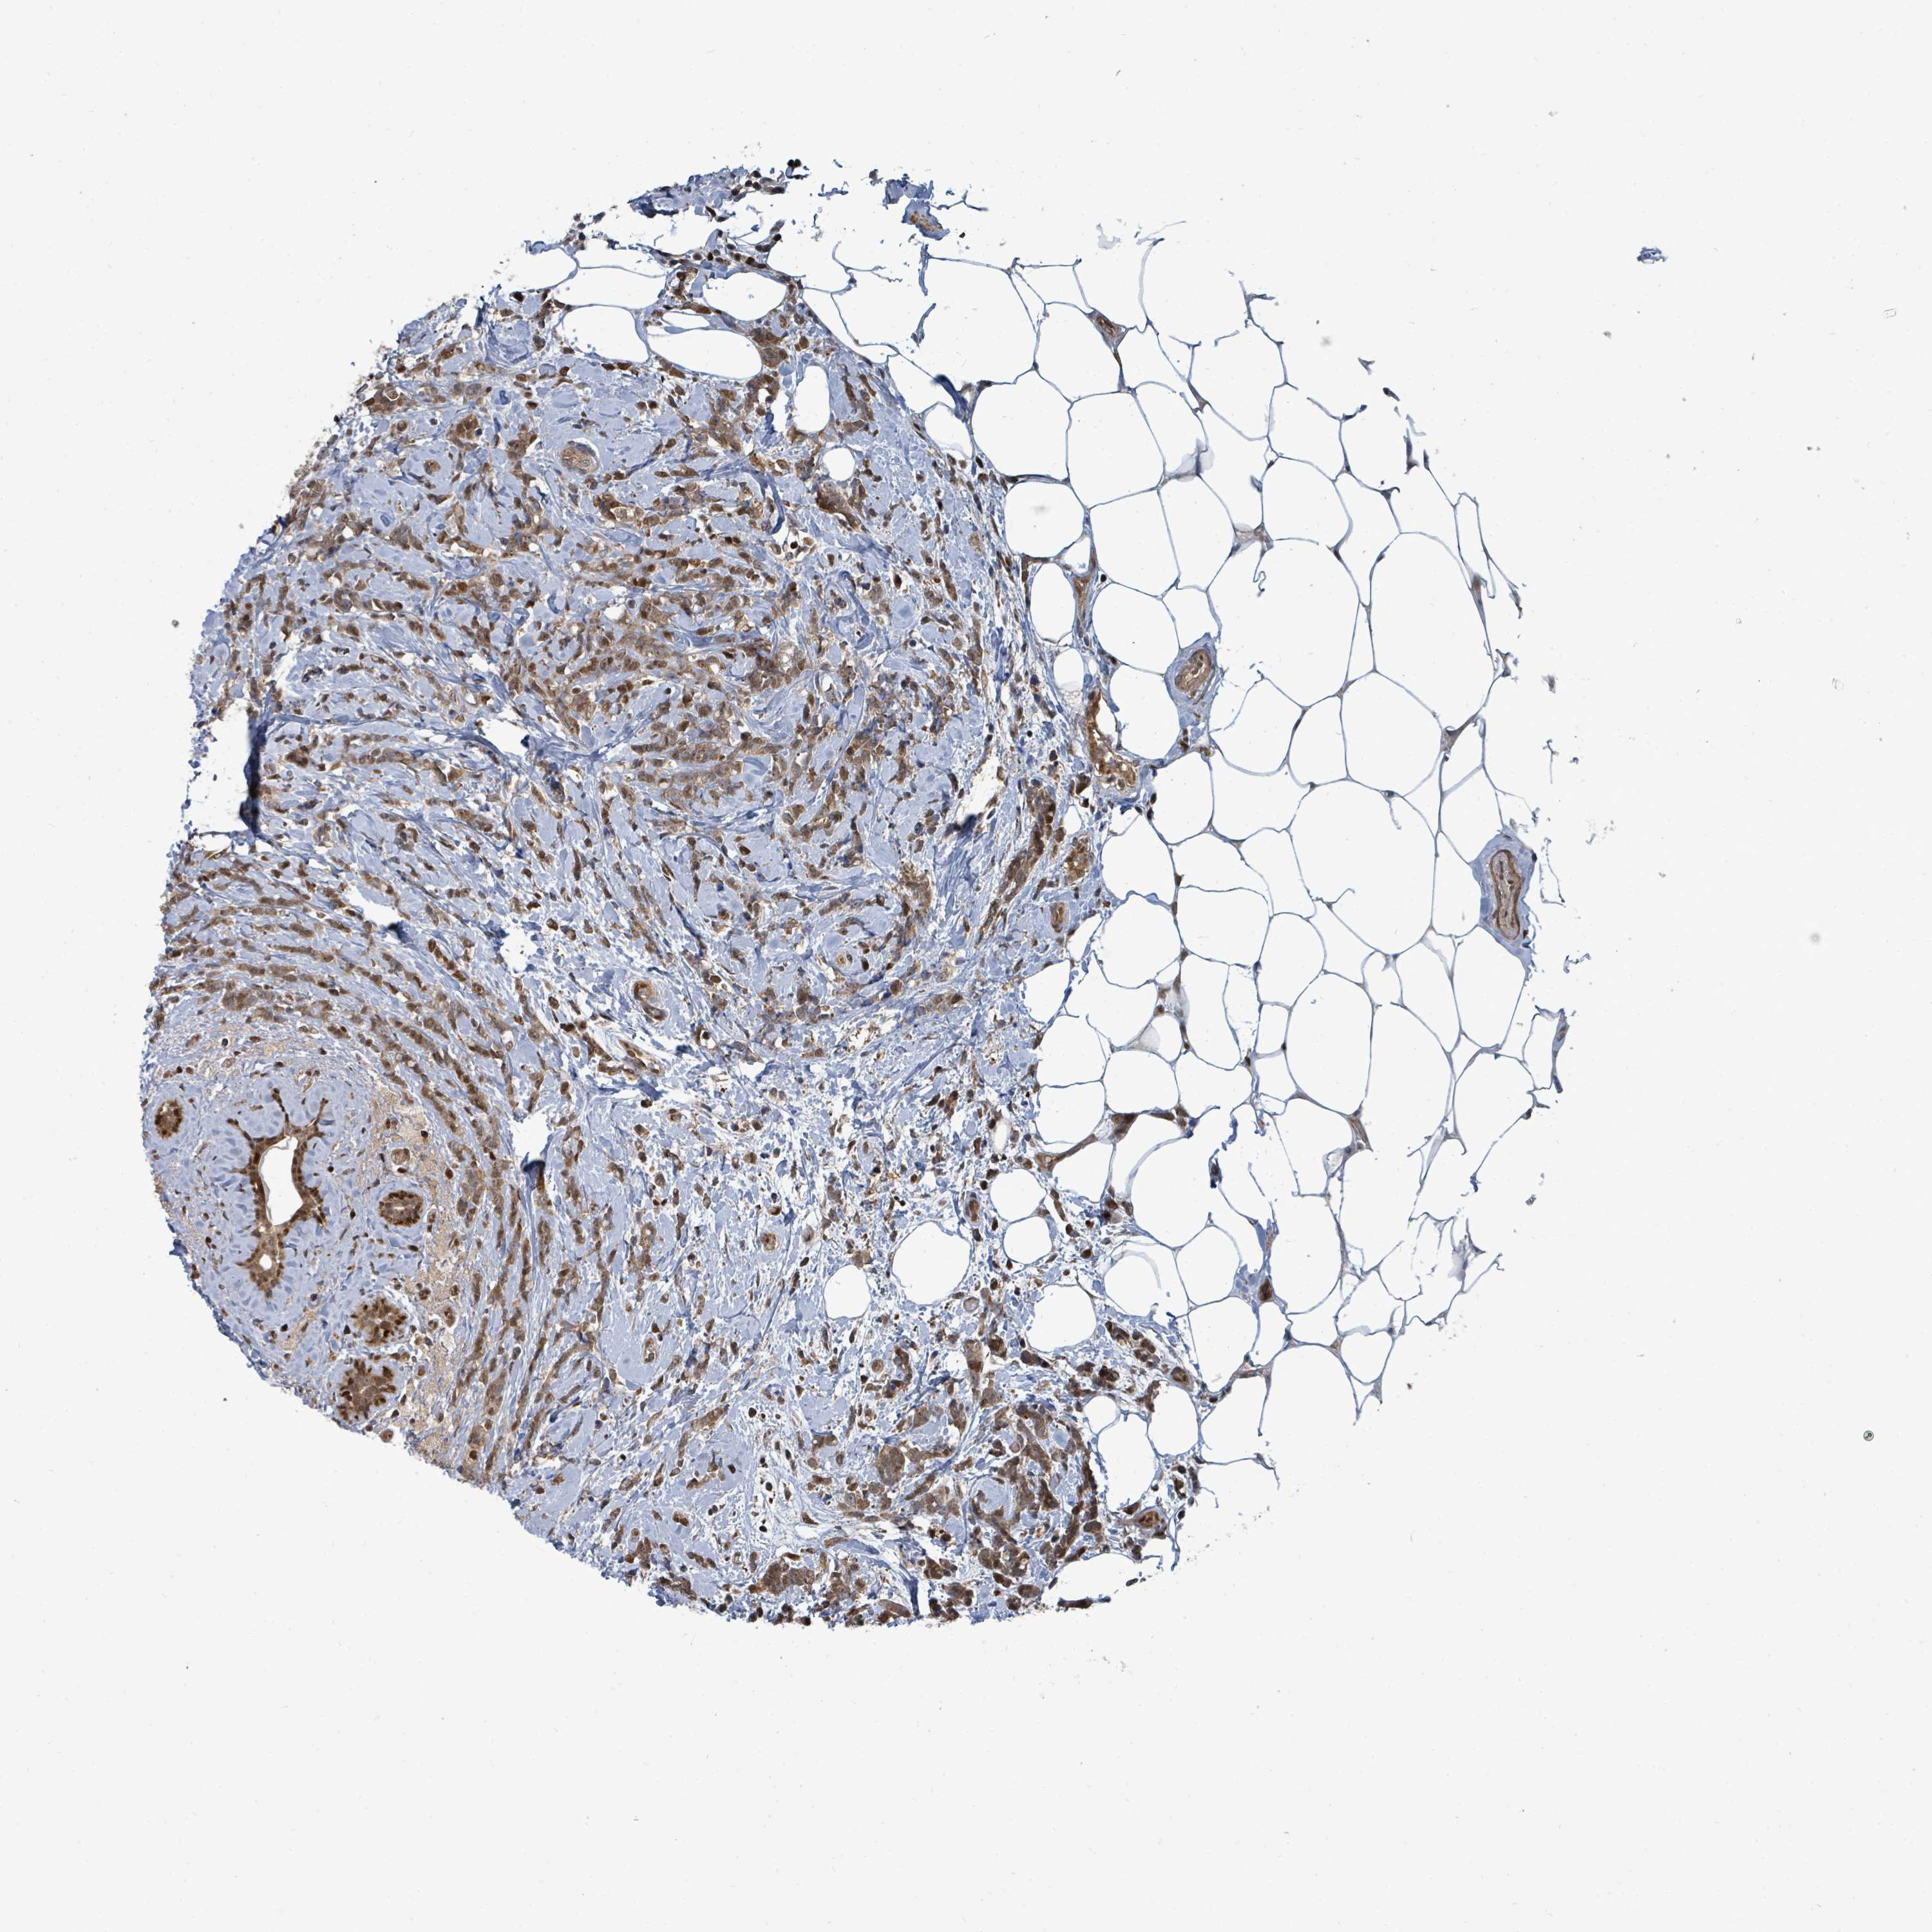

CANCER BREAST CANCER Show tissue menu

BRCA TCGA BRCA VALIDATION PROTEIN EXPRESSION